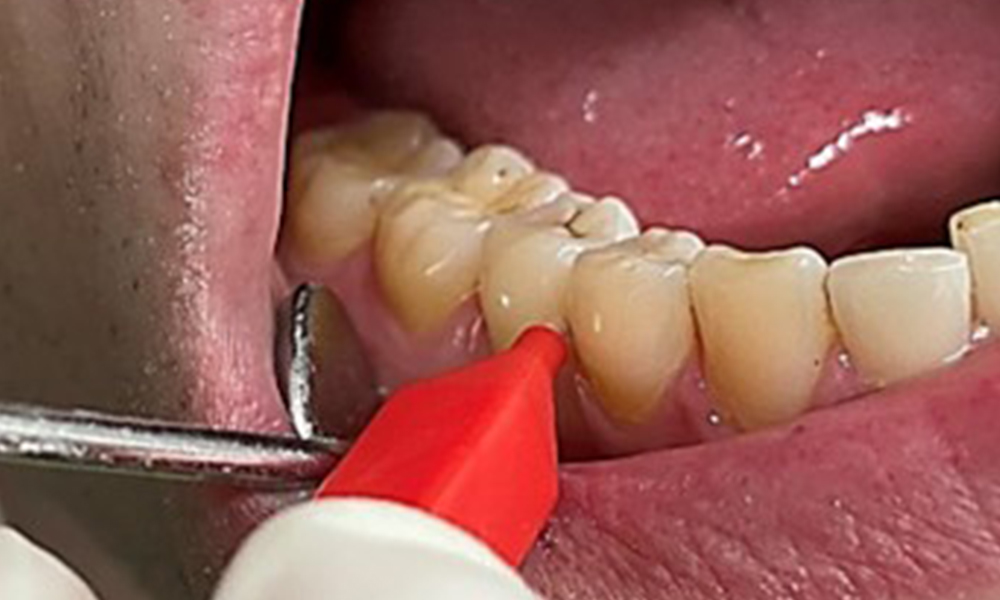

Оцветяването, причинено от консумацията на никотин и чай, може да се отстрани лесно с помощта на система за въздушно полиране (фиг. 11).

Когато се използва по-абразивна пудра е важно да се работи от цервикална към коронарна посока и никога накрайникът да не се насочва към гингивата, за да се предотврати потенциален емфизем. Доброто засмукване от контралатералната страна е от съществено значение за намаляване на образуването на аерозол (фиг. 12).